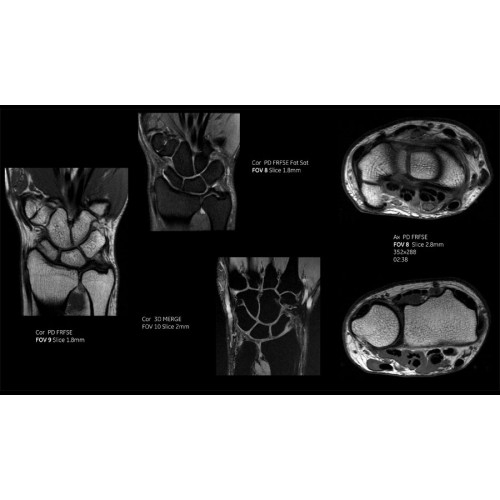

• Технология Digital Surround Technology (DST) — это новая технология объемной оцифровки данных, объединяющая сигналы от каждого элемента катушки. Прекрасное соотношение сигнал/шум и чувствительность поверхностных катушек в сочетании с превосходной однородностью и высокой проникающей способностью встроенной радиочастотной катушки — все это позволяет создавать качественные изображения не только позвоночника, но и всего тела.

Благодаря революционному программному пакету Silent Suite уровень шума снижается до 77 дБ, что всего на 3 дБ выше уровня окружающей среды. Программный пакет Silent Suite теперь включает полный пакет приложений для исследования ЦНС (T1, T2 FLAIR, DWI10, МРА). Кроме того, мы расширили возможности визуализации Silent за пределы ЦНС для исследований скелетно-мышечной системы и позвоночника. Silent Suite – платформа, содержащая в себе все импульсные последовательности для бесшумного сканирования.